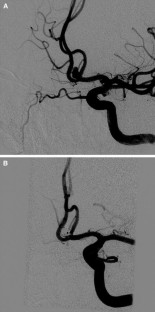

Fig. 1